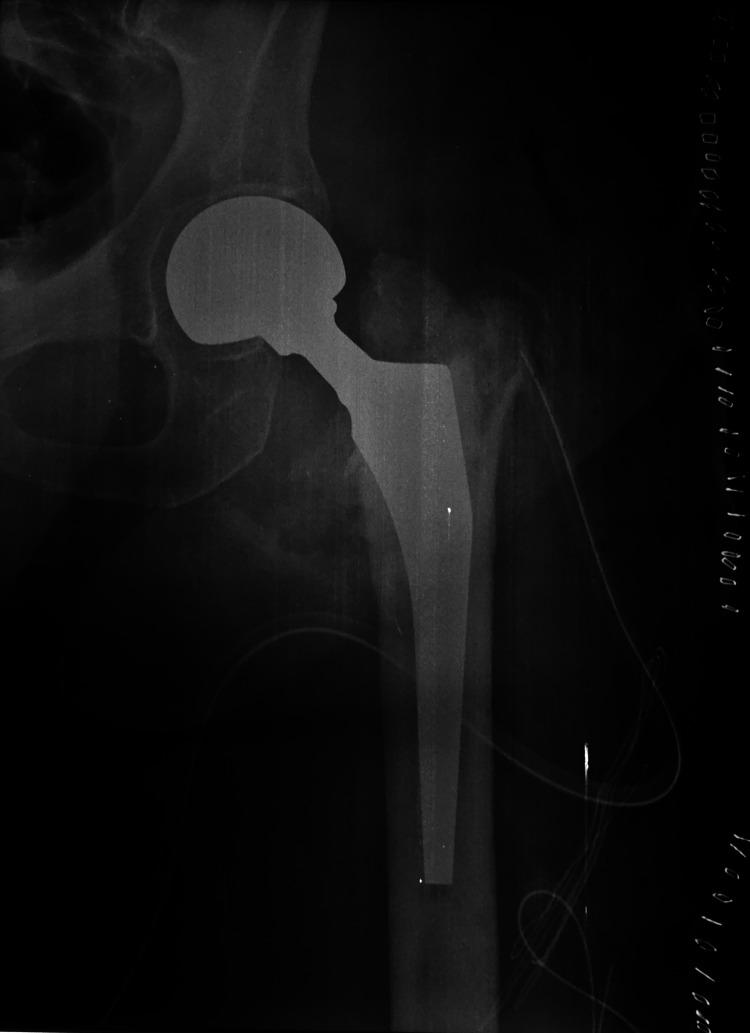

Intramedullary nailing is an established method for treating pertrochanteric fractures. However, the widespread use of this technique comes along with a variety of complications. We present a case of a 50-year-old female who presented to the emergency department suffering a left pertrochanteric fracture. She was treated with proximal femoral nailing and discharged home. Nine months later, she presented again to the emergency department with pain and an inability to bear weight. Imaging revealed the mechanical failure of the hip screw and loss of fracture fixation. Revision surgery included extraction of the broken hardware and a left hip hemiarthroplasty. The removed implant was sent for further evaluation. Fractographic analysis showed acute breakage due to bending and torsion forces acting on the screw with no relevant signs of metal fatigue. This biomechanical method is of great value for the surgeon and the implant manufacturer in order to understand the failure pattern and optimize future implants and fixation techniques. Improved implant biomechanical properties together with meticulous surgical technique constitute the cornerstones for optimal results.

髓内钉固定术是治疗转子间骨折的一种成熟方法。然而,这项技术的广泛应用伴随着各种并发症。我们报告一例50岁女性,因左侧转子间骨折就诊于急诊科。她接受了股骨近端钉固定治疗后出院回家。九个月后,她再次因疼痛和无法负重就诊于急诊科。影像学检查显示髋螺钉出现机械故障,骨折固定失效。翻修手术包括取出断裂的内固定器械并进行左侧髋关节半关节置换术。取出的植入物送去做进一步评估。断口分析显示,螺钉因弯曲和扭转力导致急性断裂,无明显金属疲劳迹象。这种生物力学方法对于外科医生和植入物制造商理解失效模式以及优化未来的植入物和固定技术具有重要价值。改善植入物的生物力学性能并辅以细致的手术技术是取得最佳效果的基石。